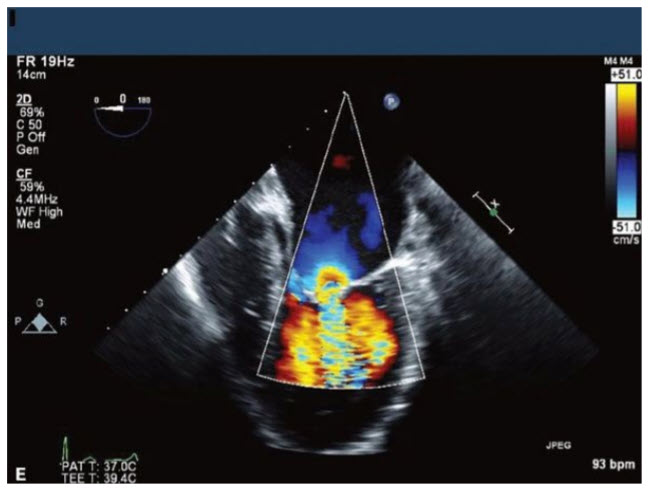

The images in Figure below A–E come from an 18-year-old young man with marked shortness of breath (SOB).

The most appropriate course of action would be

A. Closed mitral commissurotomy because he has a split score of 0 to 4 and minimal mitral regurgitation (MR)

B. Percutaneous mitral valvuloplasty (PMV) because he has a split score of 4 to 8 and minimal MR

C. Surgical MVR because he has a split score of 8 to 12 and minimal MR

D. Surgical MVR because he has a split score of 0 to 4 with significant MR

E. Surgical MVR because he has a split score of 4 to 8 and significant MR